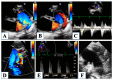

Hypoplastic left heart syndrome is a spectrum of complex congenital cardiac defects. Although in borderline cases, biventricular repair is a viable option, in the majority of cases, univentricular palliation is the treatment of choice. Hybrid palliation can be a valid alternative to classic Norwood operation in the neonatal period, especially in selected cases such as high-risk patients or borderline left ventricles. Echocardiography is the main diagnostic modality in this pediatric population, from the fetal diagnosis to the subsequent surgical steps of palliative treatment. Hybrid palliation is performed after birth and is characterized by surgical banding of the pulmonary arteries along with transcatheter stenting of the ductus arteriosus. There are some peculiar aspects of cardiac imaging that characterize this type of palliation, and that should be considered in the different phases before and after the procedure. We aimed to review the current literature about the role of echocardiography in the management of patients with hypoplastic left heart undergoing hybrid palliation.